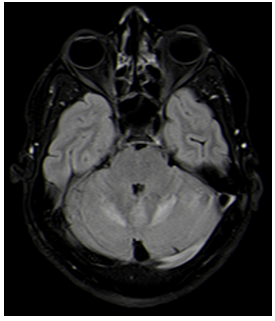

A 40-year old gentleman with well controlled Type 2 Diabetes Mellitus (T2DM) on oral hypoglycemic agent presented in January 2020 with fever, headache, multiple episodes of vomiting since 1 month and neck pain since last 2 days. Fever was intermittent. Headache was frontal, dull aching, non-radiating, mild to moderate in severity, increased when turning towards right and flexion of head. Patient is a resident of Delhi NCR and had a recent travel history to the urban areas in Uttar Pradesh and Gujarat. There was no history of skin rash or abscesses, injury or high-risk behavior. During illness, patient had consulted local doctors and was treated with antibiotics with no significant improvement. On examination, patient was conscious, well oriented to time, place and person; vitals were stable, afebrile. On systemic examination, no abnormalities were detected. On neurological examination, neck rigidity was present; higher mental functions were normal with no cranial nerve abnormalities. Patient had no motor deficit, power- 5/5 in all limbs, extensor planter response, and normal fundus examination. Laboratory reports revealed TLC 11,100 cells/cm3 with normal CRP, ESR (7mm/hour), kidney function test, and HbA1c-6.3%. Contrast MRI brain screening revealed multifocal areas of signal alteration and enhancement in supratentorial brain parenchyma, brainstem and cerebellum. The imaging findings were reported to be suggestive of infective etiology with possibility non-specific viral encephalitis/cerebellitis (Figure 1). MRI spine contrast cervical revealed mild degenerative spondylotic changes; abnormal signal and enhancement in bilateral cerebellum; no significant spinal stenosis, cord compression; no abnormal leptomeningeal or intramedullary enhancement; no significant focal intramedullary lesion detected.

Figure 1 MRI brain suggestive of multifocal areas of signal alteration and enhancement in supratentorial brain parenchyma, brainstem and cerebellum.